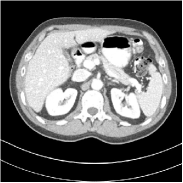

Fig. 2 shows a test example reconstructed using various methods.

Refer to caption

Figure 2: Reconstructions of slice 100 from patient L192 using various methods. The display window is [800 1200] HU.

We observe that PWLS-EP reduces the severe noise and streak artifacts observed in the low-dose FBP images, and the transform learning-based method PWLS-ULTRA further suppresses noise and reconstructs more details of the image such as the zoom-in areas. However, both methods have some blurry artifacts. The standalone FBPConvNet method heavily removes noise and streak artifacts, while introducing several artificial features (e.g., feature indicated by the arrow in the top-right box in Fig. 2). WavResNet denoises the image without introducing artifical features, but still retains some streaks around image boundaries and blurs some details (e.g., feature indicated by the arrow in the bottom-left box in Fig. 2). The state-of-the-art MAP-NN method performs slightly better than WavResNet in terms of suppressing streak artifacts, while it still loses some details as indicated in the zoomed regions. The competing plug-and-play unrolled method—ADMM-Net with WavResNet denoiser—outperforms the standalone WavResNet method, but still has some streak artifacts and blurred details. Compared to these methods, the proposed SUPER methods (SUPER-WRN-EP, SUPER-WRN-ULTRA, SUPER-FCN-EP, and SUPER-FCN-ULTRA) improve the reconstruction quality in terms of removing noise and artifacts, and recovering details more precisely. Two other example comparisons are included in the supplement (Fig. 10 and Fig. 11).